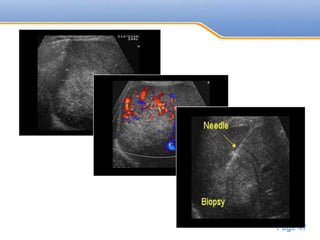

• #25 A 60 year old male patient with known chronic hepatitis C and liver cirrhosis. On surveillance US, a hypoechoic lesion was noted in segment 3 of the liver and demonstrated vascularity on Doppler study.

• #55 Biopsy proven bilobed HCC in segment 8 of liver peripherally located with invasion of hepatic vein pulse Doppler demonstrate arterial flow